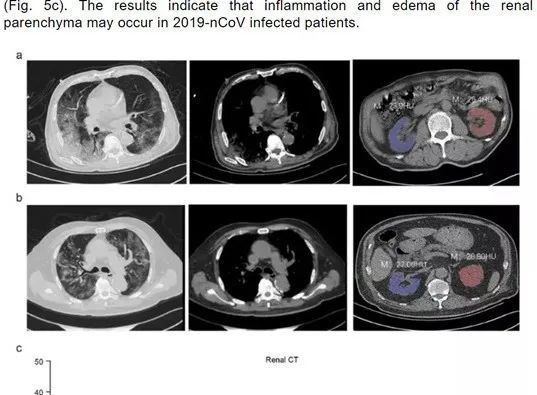

一篇《Caution on Kidney Dysfunctions of 2019-nCoV Patients》的论文 , 研究了59名感染患者病例 。 结果显示 ,63%的患者表现出肾功能不全的症状 , CT扫描显示100%的患者肾脏影像学异常 。

本文图片